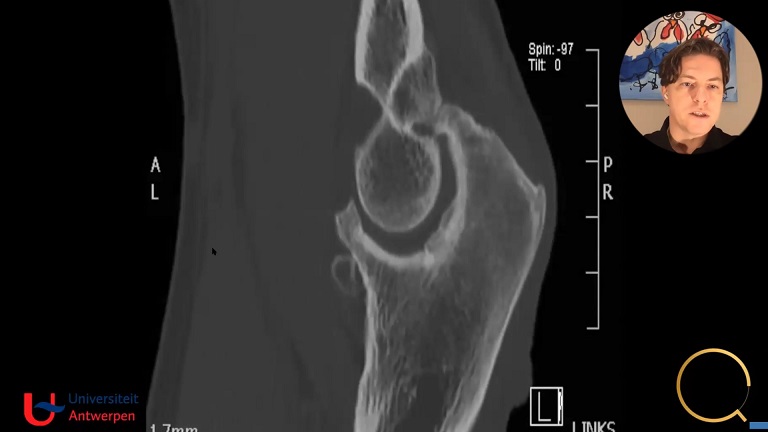

Case Presentation 1: Lateral Elbow Pain – Unstable? K. Wegmann

Case Presentation 2: Lateral Elbow Pain Due to an Unstable Elbow? C. Schoch

The Future of Operative Treatment: What’s Next? Arthroscopic Debridement, LUCL Repair, Imbrication? P. Arrigoni

Complex Case Presentation 1: Imbrication/Arthroscopic Reconstruction R. van Riet